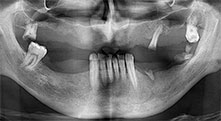

Бихте ли описали накратко, например, Вашия метод за мобилизиране на костни блокове за трансплантация?

Брату: Ние предпочитаме да събираме кост от външната страна на гребена в задната част на долната челюст. След разрязване на меките тъкани, ние използваме новите триони, за да определим количеството кост, което ще събираме. С този подход, ние използваме трионите за цялата препарация в почти 80% от случаите. Може да използваме и други пиезо инструменти и накрая длето за мобилизиране на блока. Ние смятаме, че това е изключително ефективна хирургична техника.